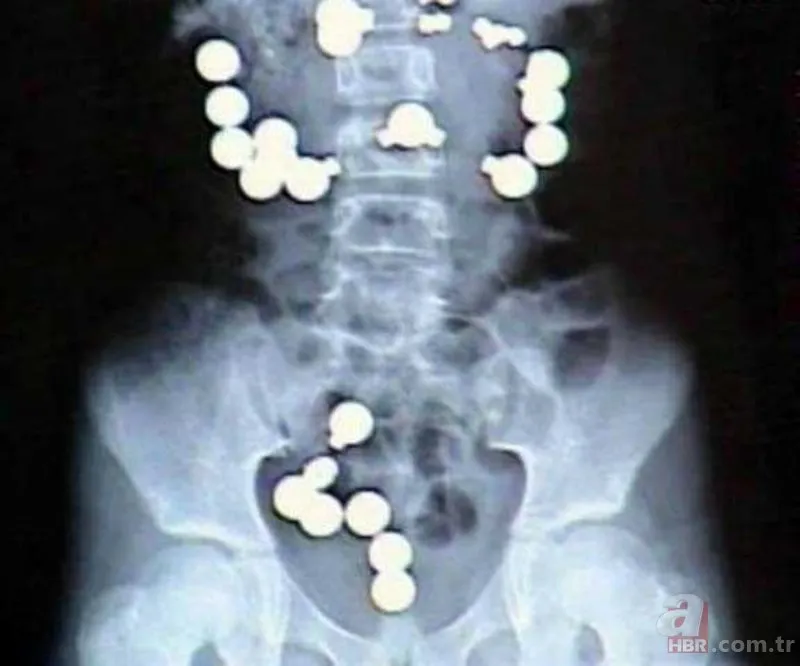

Amerika'nın Indiana eyaletinde yaşayan 8 yaşındaki bir kız çocuğu, bir gün mıknatıs ve çelik topların şeker gibi göründüğüne karar verdi. Ardından bunların hepsini, toplamda 10 mıknatıs ve 20 çelik topu yuttu. Zaten zararlı olan bu yabancı maddeler, bir de vücudunun içinde birbirine ulaşmaya çalışınca her şey daha da kötü oldu. Acilen ameliyata alınan kız çocuğunun bağırsaklarına da 8 dikiş atıldı.